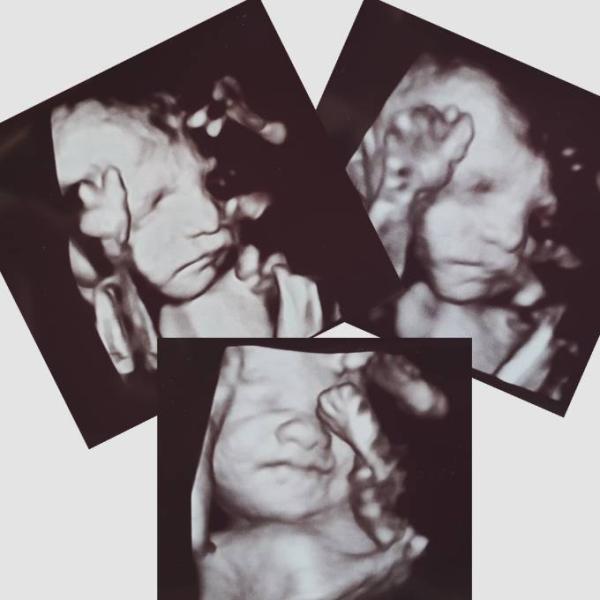

Hallo ihr Lieben Mein Herz hat heute so einen riesen Sprung gemacht, als ich unser 2.Wunder auf dem Ultraschall gesehen habe Meine Güte, ich bin immer noch ganz und gar hin und weg! Sie war so süß anzuschauen mit den Mundbewegungen und dem großen Zeh halb in der Nase Sie wiegt ca. 1400g und misst ca. 38,5cm und man konnte sogar Haare erahnen Rundum zufrieden bin ich, trotz eines kleinen Harnstaus, was aber auch wieder weggeht mit Wärme etc. Danach kam die Hebamme zu uns und hat auf Grund meiner Rückenschmerzen ein paar Schmerzpunkte akupunktiert und wir haben noch mal über die Geburt gesprochen. Also heute war Rundumprogramm Seid alle lieb gegrüßt

Bild zu Großer Ultraschall und Akupunktur 🥰 - Forum für Januar - Mamis